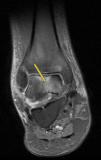

Caso clínicoVarón de 41 años, sin antecedentes de interés, que acudió refiriendo gonalgia derecha, frente a traumatismo mínimo. En la RMN se apreció edema óseo difuso en cóndilo externo. Cuatro meses después surgió edema óseo en cóndilo interno ipsilateral (fig. 1). Posteriormente, en otras resonancias, hallamos nuevo extenso edema óseo, ahora en cóndilo femoral interno de rodilla contralateral, luego en cóndilo externo y dolor en tobillo derecho, en cuya RMN también se apreciaba edema óseo, en astrágalo (figs. 2 y 3). Se instauró tratamiento con AINE, y carga parcial, siendo ineficaz.

En el diagnóstico diferencial es interesante su distinción respecto de la algodistrofia de Südeck, distrofia simpático refleja o síndrome de dolor regional complejo. Esta entidad cursa con dolor tras un evento traumático, a veces de poca intensidad, presentando alodinia (o dolor intenso en respuesta a estímulos no dolorosos), hiperalgesia, así como, trastornos vasomotores de compromiso vegetativo. En una osteoporosis transitoria migratoria no se manifiesta este cortejo vegetativo. Por otro lado, el edema medular óseo se presenta como un patrón de imagen en la RMN. caracterizado por hiposeñal en T1 e hiperseñal en STIR T2 en médula ósea. Cuando este edema aparece en varias articulaciones, sin imágenes de osteonecrosis, y no de forma aislada, estaríamos ante una osteoporosis transitoria migratoria.